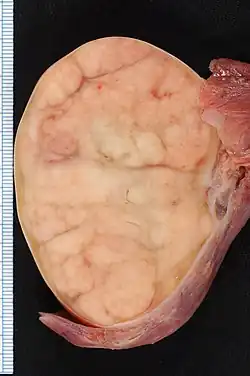

The tumor is uniform in appearance, consisting of large, round cells with vesicular nuclei and clear or finely granular cytoplasm that is eosinophilic. On gross examination, the external surface is smooth and bosselated (knobby), and the interior is soft, fleshy, and either cream-coloured, gray, pink, or tan. Microscopic examination typically reveals uniform cells that resemble primordial germ cells. Typically, the stroma contains lymphocytes, and about 20% of patients have sarcoid-like granulomas.